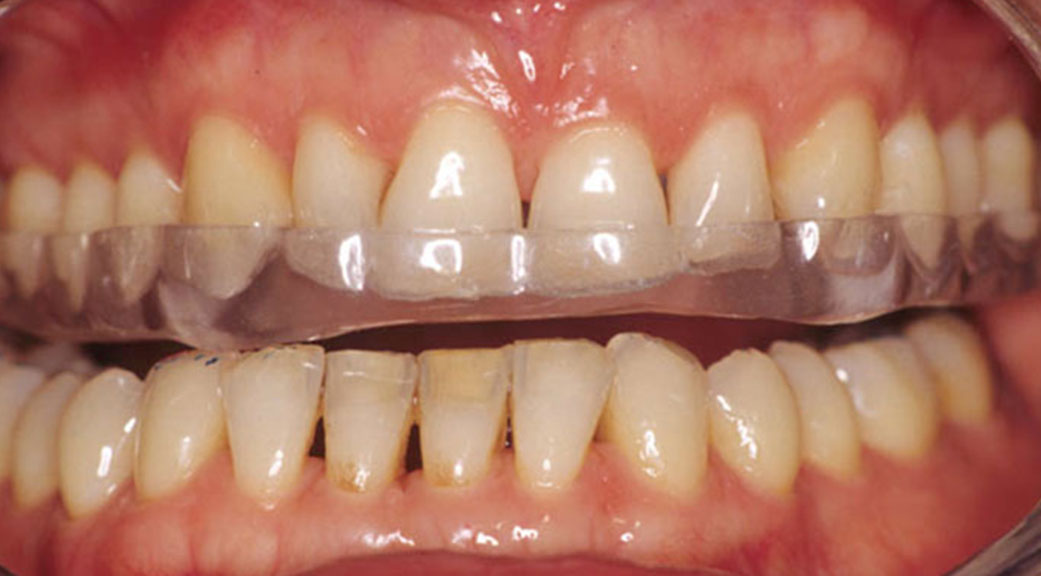

Bruxisme et usure dentaire